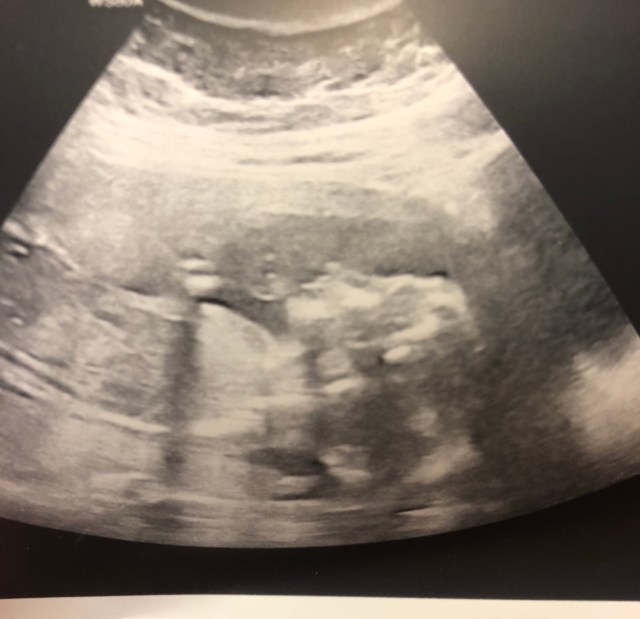

Mummy and Daddy went to their 12 week scan feeling really positive. The scan was going well but little Bean did a flip right at the last minute which revealed something a little odd. The sonographer went quiet… ‘I just need to ask my colleague to have a look’. Cord Cysts were the tentative diagnosis. ‘But they’re so rare we don’t see them very often. I’ll have to take advice from the fetal medicine unit at Saint Mary’s and ring you to explain what they think we should do’ said the consultant.

The fetal medicine team decided that they wanted to see us and scan us with their consultants present. The diagnosis changed. ‘It looks like your baby’s bowel is inside the umbilical cord instead of inside their body’ said the consultant. ‘Because it’s only a small amount, it is more likely that it’s related to a chromosome problem. We would like to offer you a CVS or an amniocentesis to rule out any other problems’. Mummy opted for the amniocentesis- it was slightly less risky than the alternative and the extra week to wait didn’t seem like it was too long.

After a very long two weeks the results were in – Little Bean had no abnormal chromosomes… and little bean was a baby girl. Mummy and Daddy were delighted. The fetal medicine team kept a close eye on mummy and bean every month to make sure that bean’s growth was normal and that the bowel problem still stable -sometimes these things can repair themselves before 20 weeks – but little Bean had other ideas and refused to show her cord insertion point to the consultants all the way up to the final scan at almost 36 weeks.